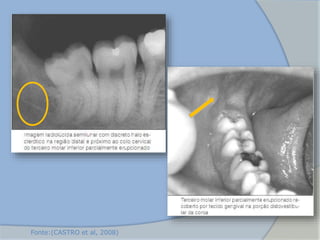

3. Cisto Paradentário

 Originado de remanescentes do epitélio reduzido do órgão do

esmalte ou de restos epiteliais de Malassez no periodonto

 Região distal dos terceiros molares inferiores (semi-inclusos e com

história prévia de pericoronarite)

 Radiograficamente: Área radiolúcida bem delimitada normalmente

localizada lateralmente (mais comum na distal) a um elemento

dentário

(CASTRO et al, 2008)

Fonte:(CASTRO et al, 2008)